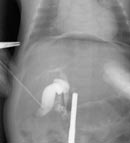

При чрезкожной чрезпеченочной холецистохолангиографии контрастируется желчный пузырь извитой в области тела и шейки, расширенный до 0,9 см общий желчный проток, общий печеночный и правый печеночный протоки с сегментарными ветвями. В просвете общего желчного протока несколько дефектов контрастирования, подобных конкрементам, хорошо смещаемых. Котрастное вещество в 12-перстную кишку не поступает (Рис. 4). При манипуляции лапароскопическим инструментарием и повышении гидростатического давления в билиарной системе получен сброс контрастного вещества в 12-перстную кишку, при этом ширина холедоха уменьшилась (Рис. 5).

Рис. 4. Чрезкожная чрезпеченочная холецистохолангиография под контролем лапароскопа (контрастное вещество в 12-перстную кишку не поступает).

Рис. 5. Чрезкожная чрезпеченочная холецистохолангиография под контролем лапароскопа (контрастное вещество в 12-перстной кишке).

Ребенок осмотрен спустя 3 месяца после манипуляции - по данным УЗИ общий желчный проток - 3,7 мм.